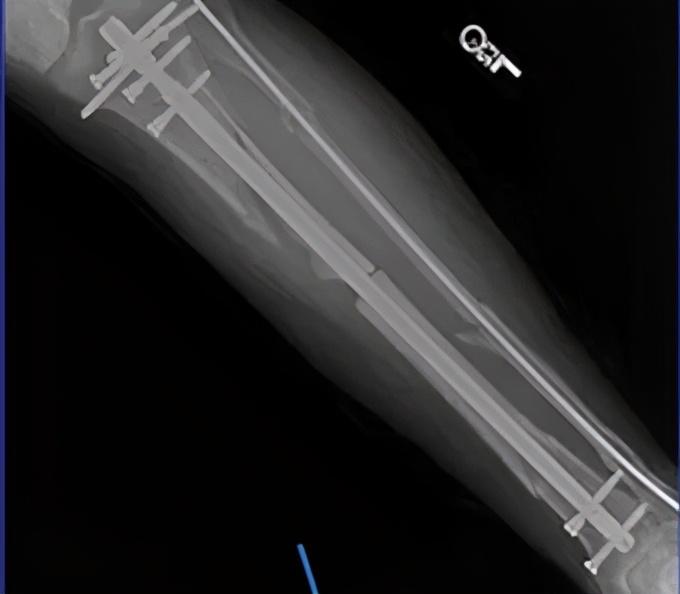

2014年

乔治在一次追身封盖詹姆斯·哈登的过程中

落地时右腿撞到篮架直接扭曲

导致胫骨腓骨开放性骨折

下图请谨慎观看

容易造成不适